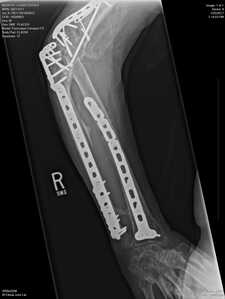

Some serious hardware. ( I had some bit a small percentage of yours. )